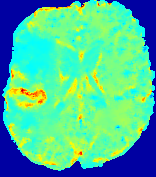

Slice #1Slice #2Slice #3Slice #4Slice #5Slice #6Dgtsuperscript𝐷gtD^{\text{gt}}Refer to captionRefer to captionRefer to captionRefer to captionRefer to captionRefer to captionDestsuperscript𝐷estD^{\text{est}}Refer to captionRefer to captionRefer to captionRefer to captionRefer to captionRefer to captionRefer to caption0.300.300.300.240.240.240.180.180.180.120.120.120.060.060.060.000.000.00(mm2/s)𝑚superscript𝑚2𝑠(mm^{2}/s)𝐕est𝟐subscriptnormsuperscript𝐕est2\|\bf{V}^{\text{est}}\|_{2}Refer to captionRefer to captionRefer to captionRefer to captionRefer to captionRefer to captionRefer to caption0.00300.00300.00300.00240.00240.00240.00180.00180.00180.00120.00120.00120.00060.00060.00060.00000.00000.0000(mm/s)𝑚𝑚𝑠(mm/s)

Figure 15: PIANO identifiability testing: diffusion imaging via advection-diffusion. Top row shows Dgtsuperscript𝐷gtD^{\text{gt}} used for simulating ground truth pure diffusion. Rows below show the estimated Destsuperscript𝐷estD^{\text{est}} and 𝐕est2subscriptnormsuperscript𝐕est2\|{\bf{V}}^{\text{est}}\|_{2} on corresponding slices. Note that the plotted value scale for 𝐕est2subscriptnormsuperscript𝐕est2\|{\bf{V}}^{\text{est}}\|_{2} is 0.01 of that for Dgtsuperscript𝐷gtD^{\text{gt}} and Destsuperscript𝐷estD^{\text{est}}.

Similarly, we test the behavior of PIANO when estimating both advection and diffusion from a pure diffusion-driven process. The goal is to determine if PIANO is able to recognize that there is only diffusion governing the given concentration time-series. We use the same ‘Diffusion Imaging’ data simulation of Sec. 4.2.1 as the concentration dataset, PIANO estimates both velocity 𝐕estsuperscript𝐕est{\bf{V}}^{\text{est}} and diffusivity Destsuperscript𝐷estD^{\text{est}}. Estimation results in Fig. 15 confirm PIANO’s identifiability again: the estimated 𝐕est2subscriptnormsuperscript𝐕est2\|{\bf{V}}^{\text{est}}\|_{2} is almost invisible compared to Destsuperscript𝐷estD^{\text{est}}, even plotted with a 1%percent11\% value range compared to that for Destsuperscript𝐷estD^{\text{est}}. On the other hand, Destsuperscript𝐷estD^{\text{est}} achieves comparable estimation performance as ‘Diffusion Imaging via Diffusion’ in which PIANO predicts Destsuperscript𝐷estD^{\text{est}} alone (shown in Fig. 13).